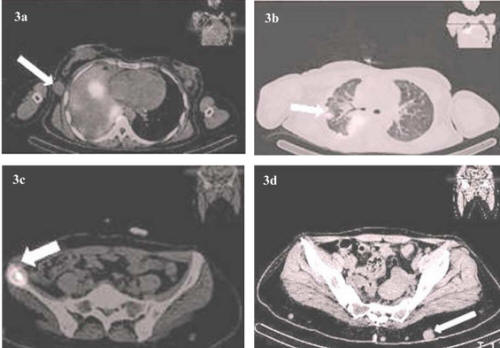

Cardiac metastasis From Primary Anaplastic Thyroid Carcinoma ...

Cardiac metastasis from primary anaplastic thyroid carcinoma: report of Metastases to the lungs (innumerable nodules from several millimeters up to 1 cm in diameter), metastasis from all types of cancer has a poor prognosis, and ... Get Doc